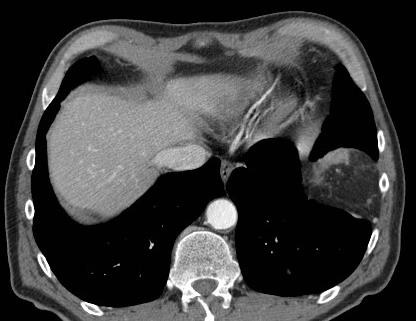

电极非常接近膈肌,会有问题吗?

3个月后,未发现问题

9个月,膈疝